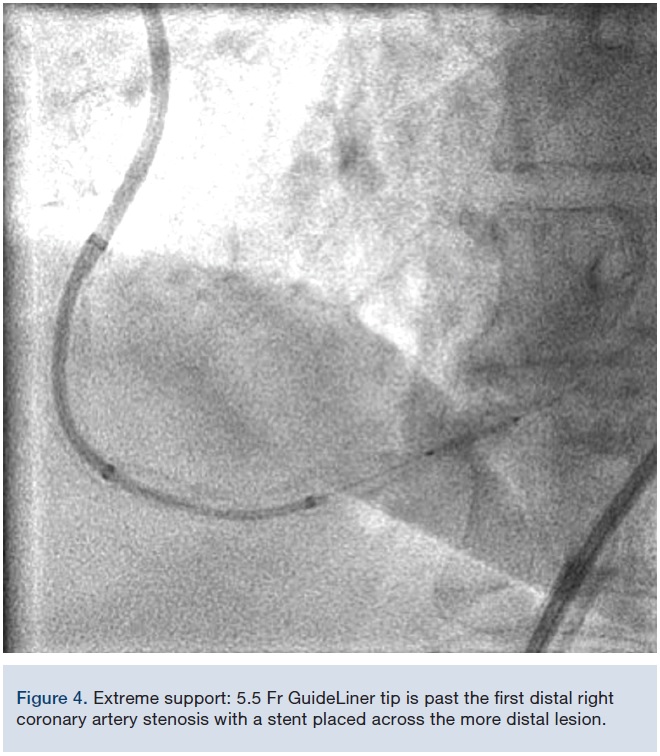

A 78-year-old male with a history of hypertension, hyperlipidemia, and coronary artery disease (CAD) presented to the office with complaints of severe fatigue and dyspnea on exertion. Patient underwent coronary artery bypass surgery 4 years ago. His left internal mammary artery was anastomosed to the diagonal branch, with 2 vein grafts anastomosed to the LAD and OM. The RCA was not bypassed, but was known to be a chronic total occlusion (CTO). The patient was treated with aspirin, amlodipine, isosorbide, simvastatin, and lisinopril. Cardiovascular exam was unremarkable. An echocardiogram showed a left ventricular ejection fraction of 40%. An EKG was normal. Angiography showed a 40% distal left main artery stenosis,

proximal 100% occlusion of the LAD, and 70% proximal stenosis of the OM. All bypass grafts were patent. CTO PCI of the RCA was begun with an 8 Fr, 45 cm sheath via the femoral artery and Amplatz left 0.75 8 Fr guide catheter. A Pilot 200 guidewire (Abbott Vascular) was used to traverse the proximal cap and MiracleBros 6 wire (Asahi Intecc) was needed for distal cap crossing. An attempt at crossing the proximal cap with a small balloon was unsuccessful due to inadequate support. A similar telescopic system was used, as described in Case 1. Once an 8 Fr GuideLiner with a 6 Fr GuideLiner extension was inserted into the proximal RCA, the balloon crossing was relatively easy (Figure 5). PCI was concluded with a good result (Figure 6) and the patient was asymptomatic afterwards.